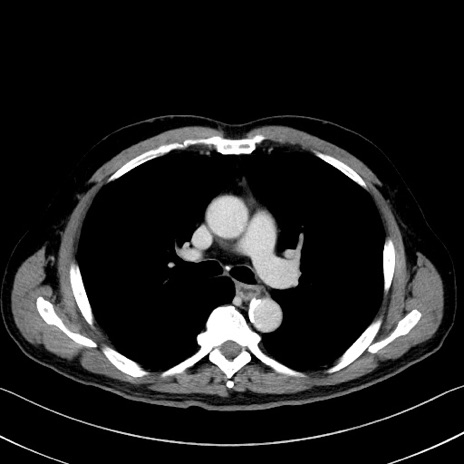

症例35(横断像)

【症例】70歳代 男性

【主訴】腹部膨満、嘔吐

【現病歴】昨日より腹部膨満感出現。本日増悪し、仙痛出現。嘔吐あり、受診。

【既往歴】糖尿病、胆摘後

【身体所見】BP 149/80mmHg、HR 74/min、BT 35.9℃、腹部:膨満、軟、圧痛なし。腸雑音減弱あり。上腹部正中切開瘢痕あり。

【データ】WBC 13500、CRP 1.72